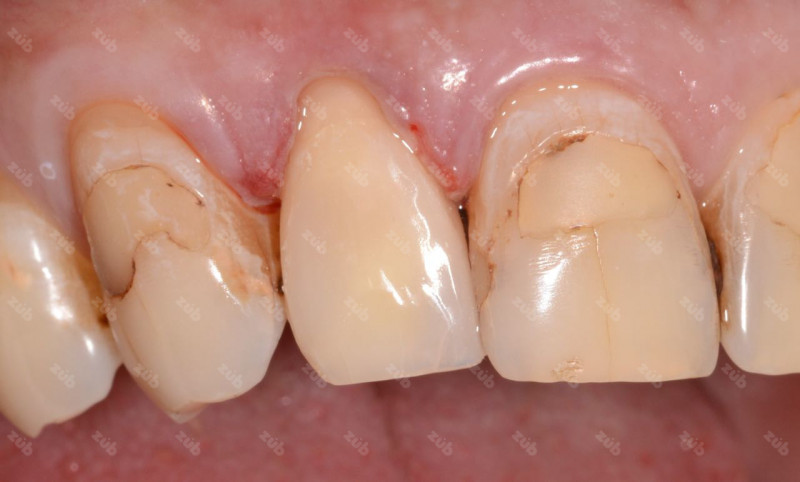

Стоматология ЗУБ (ZUB)

Профгигиена

Все работы клиники